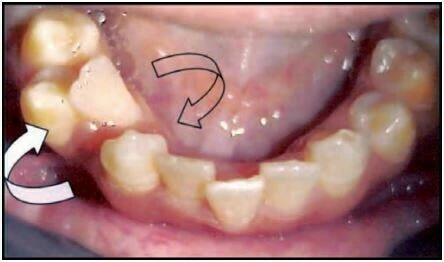

1.7 RĂNG XOAY

Đây là tình trạng những răng di chuyển xung quanh trục dọc của nó. Có hai kiểu xoay răng:

Gần trong hoặc xa ngoài

Mặt gần của răng nghiêng vào trong, hay nói cách khác mặt xa của thân răng nằm về phía ngoài so với mặt gần.

Xa trong hoặc gần ngoài

Mặt xa của răng nghiêng vào trong, hay nói cách khác mặt gần của thân răng nằm về phía ngoài so với mặt xa của nó.

Thuật ngữ này dùng để chỉ những trường hợp hai răng bị đổi chỗ cho nhau, chẳng hạn răng nanh đổi vị trí cho răng cửa bên.